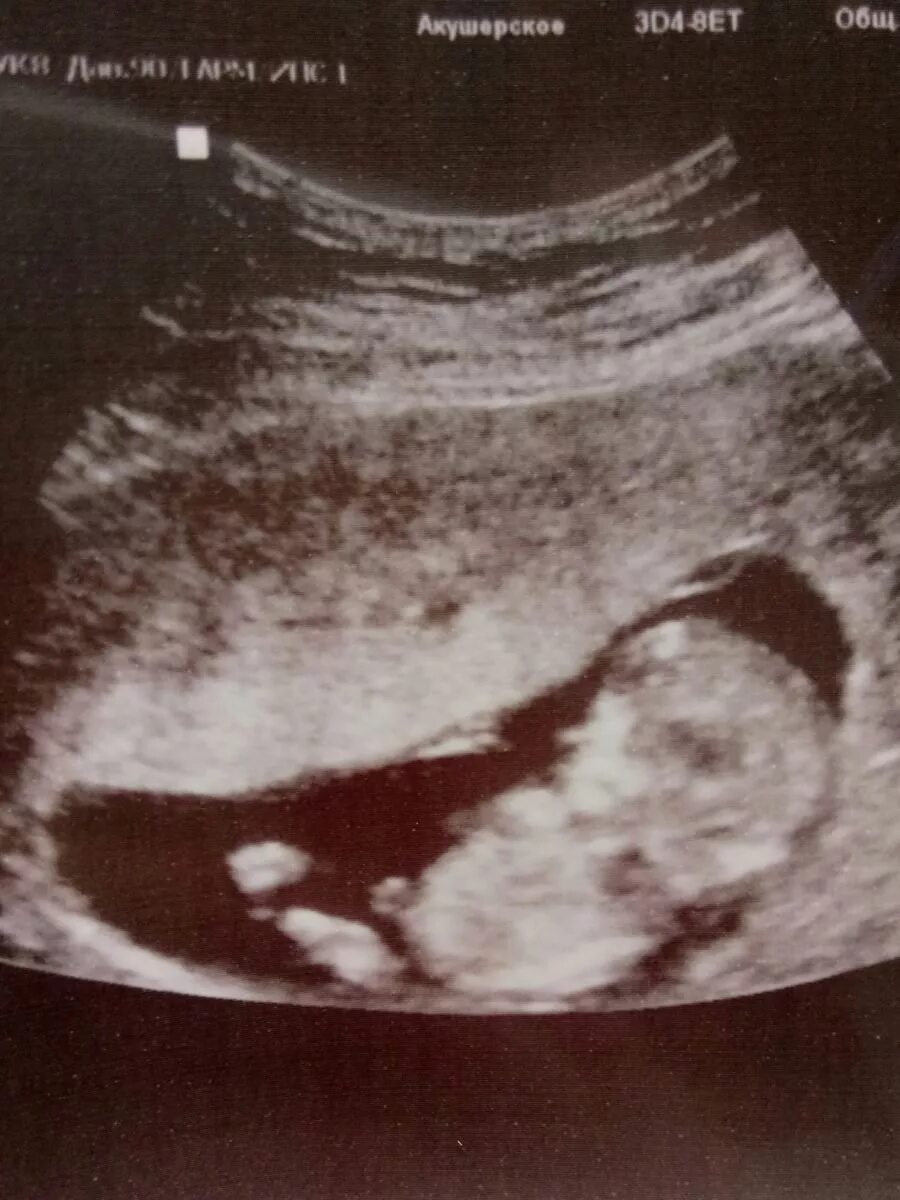

12 недель и два дня